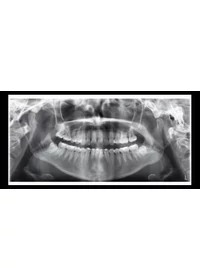

Képalkotási programok

A Planmeca ProOne® sokfajta képalkotási programot kínál a különböző röntgenigényekhez. Kiválaszthatja a megfelelő felvételi formátumokat is, hogy minimálisra csökkenjen a sugárzási dózis mindenféle beteg és diagnosztikai cél esetén.